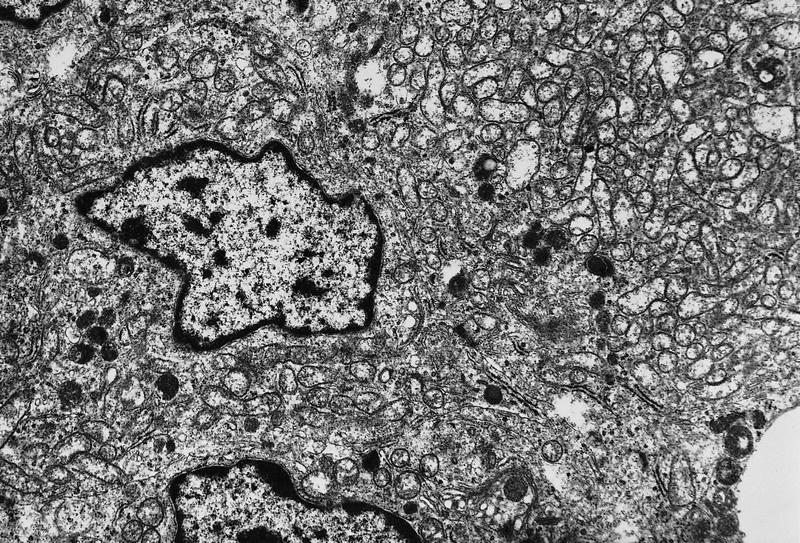

Electron microscopy description

- Mitochondria rich cytoplasm with electron dense granules and rough endoplasmic reticulum